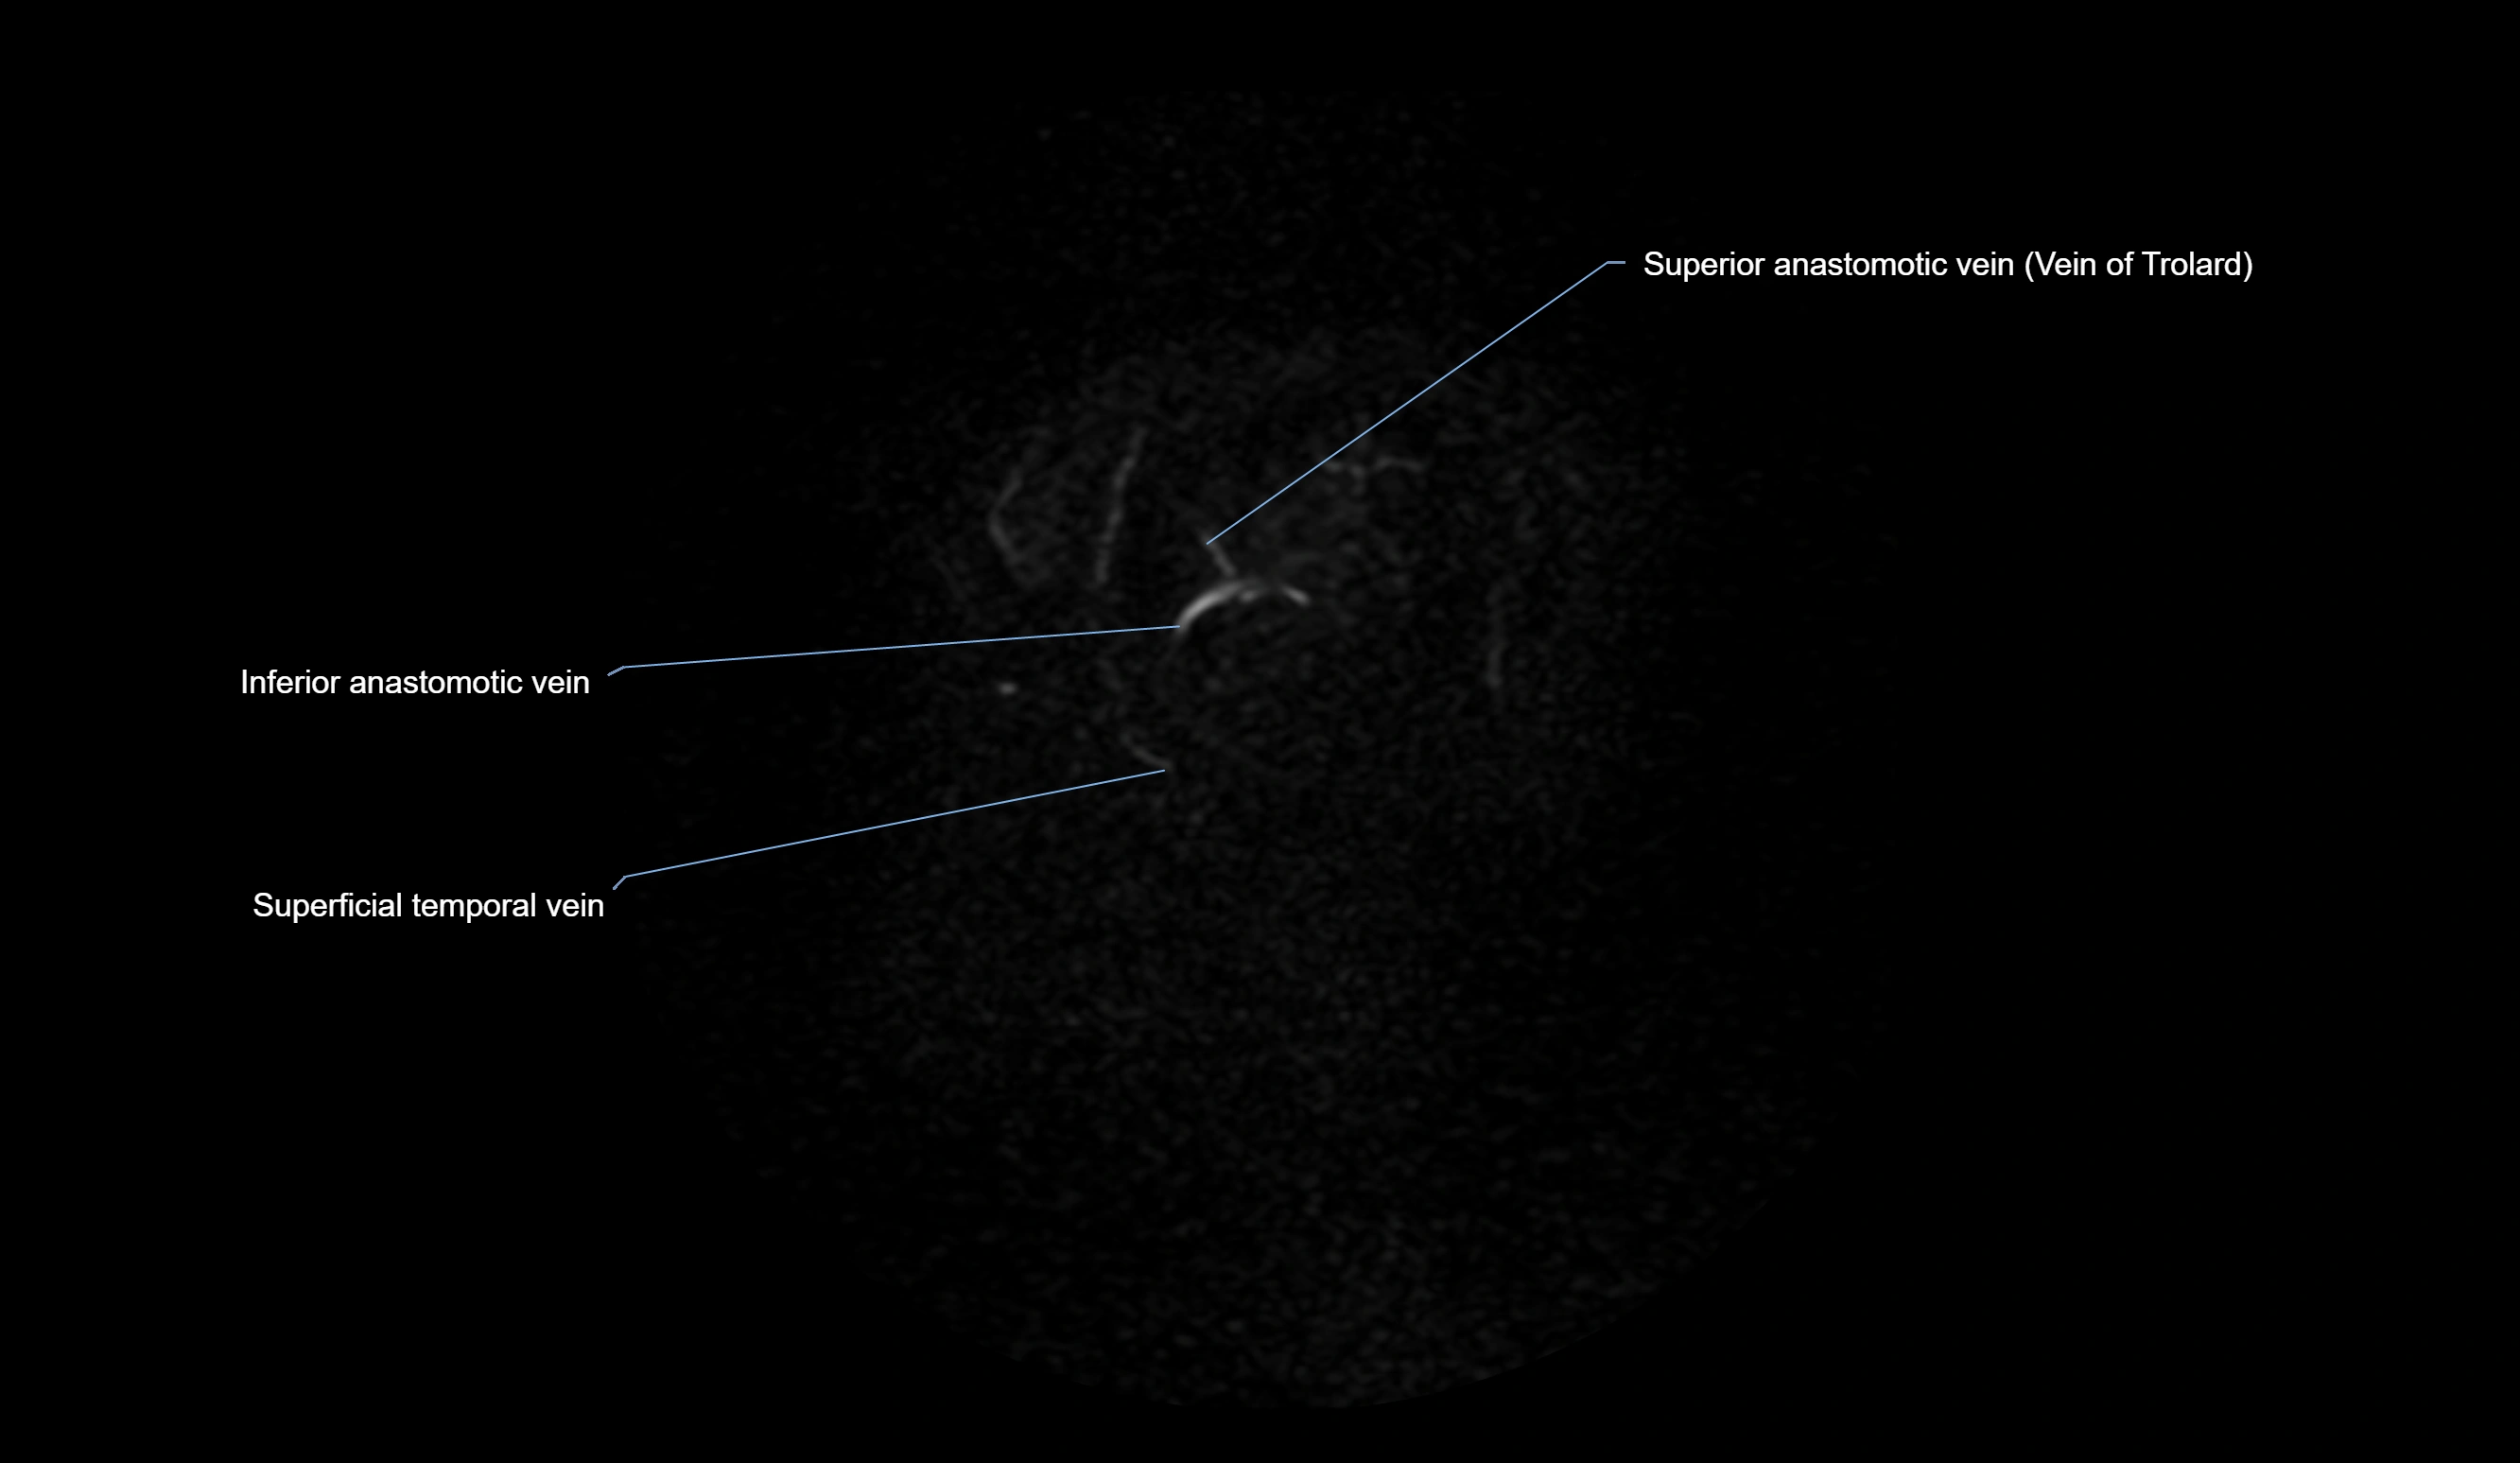

MR Venography (MRV):

• Time-of-flight (TOF) or contrast-enhanced MRV shows the angular vein as a bright enhancing venous channel

• Clearly demonstrates its continuity with the facial vein and superior ophthalmic vein

• MRV is highly useful in evaluating thrombosis, venous obstruction, or collateral venous drainage

MRI images